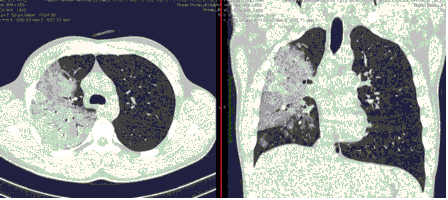

КТ имеет высокую чувствительность в выявлении изменений в легких, характерных для COVID-19. Применение КТ целесообразно для первичной оценки состояния ОГК у пациентов с тяжелыми прогрессирующими формами заболевания, а также для дифференциальной диагностики выявленных изменений и оценки динамики процесса. КТ позволяет выявить характерные изменения в легких у пациентов с COVID-19 еще до появления положительных лабораторных тестов на инфекцию с помощью МАНК. В то же время, КТ выявляет изменения легких у значительного числа пациентов с бессимптомной и легкой формами заболевания, которым не требуется госпитализация. Результаты КТ в этих случаях не влияют на тактику лечения и прогноз заболевания при наличии лабораторного подтверждения COVID-19. Поэтому массовое применение КТ для скрининга асимптомных и легких форм болезни не рекомендуется. При первичном обращении пациента с подозрением на COVID-19 рекомендуется назначать КТ только при наличии клинических и инструментальных признаков дыхательной недостаточности (SpO2 < 95%, ЧДД > 22).

У больных с факторами риска, COVID-ИА следует исключить при рефрактерной к адекватной антибактериальной терапии лихорадке >= 3 дней или нового эпизода лихорадки после нормализации t тела >= 2 дней, нарастании дыхательной недостаточности, а также появлении кровохарканья, боли в груди или шума трения плевры. При COVID-ИА на КТ ли РГ легких выявляют двусторонние или односторонние очаги консолидации или деструкции. При наличии указанных клинических и радиологических признаков COVID-ИА показана бронхоскопия с получением БАЛ из пораженного сегмента, при интубации пациента возможно повторное получение трахеального аспирата (ТА) или небронхоскопического лаважа (НБЛ).

Методы лучевой диагностики применяют для выявления COVID-19 пневмоний, их осложнений, дифференциальной диагностики с другими заболеваниями легких, а также для определения степени выраженности и динамики изменений, оценки эффективности проводимой терапии.

К методам лучевой диагностики патологии ОГК пациентов с предполагаемой/установленной COVID-19 пневмонией относят: